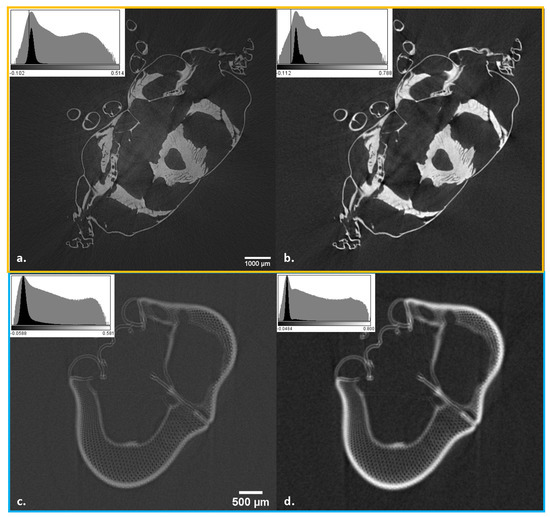

3.1. Example for the Paganin Method

3.2. Example BAC Method

3.3. Example for Grating-Based PCI